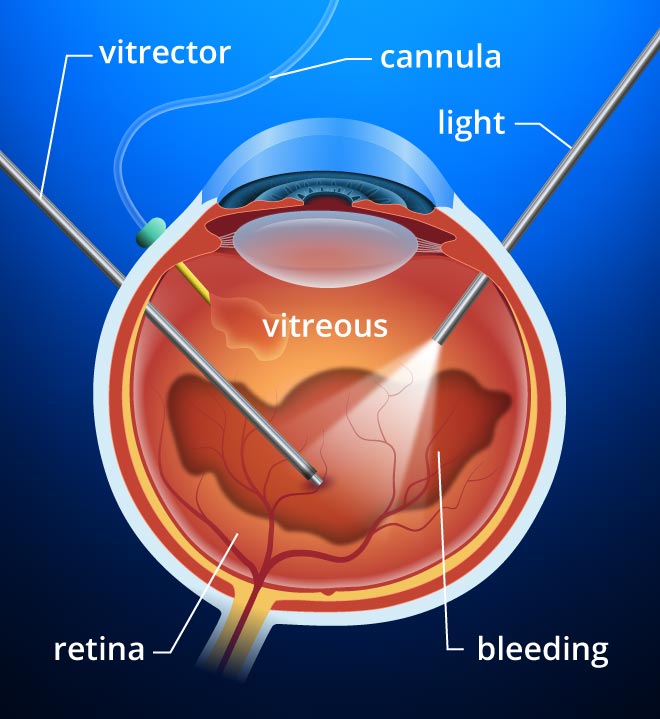

Vitreo Retinal Surgery | Retinal detachment | Endophthalmitis

1 Anatomy of the Vitreous, Retina, and Choroid | Ento Key

Surgically Induced Detachment of the Anterior Hyaloid Membrane From the …

Retinal Tear & Detachment – Retina Vitreous Consultants, Inc

Epiretinal membrane – Mayo Clinic

Epiretinal membrane definition, causes, symptoms, diagnosis & treatment

Epiretinal Membranes Diagnosis and Treatment – Kam Balaggan

Case of epiretinal membrane (ERM) in an eye with an axial length of …

Epiretinal membrane – Edgbaston Eye Clinic

Epiretinal Membrane – Retina Image Bank